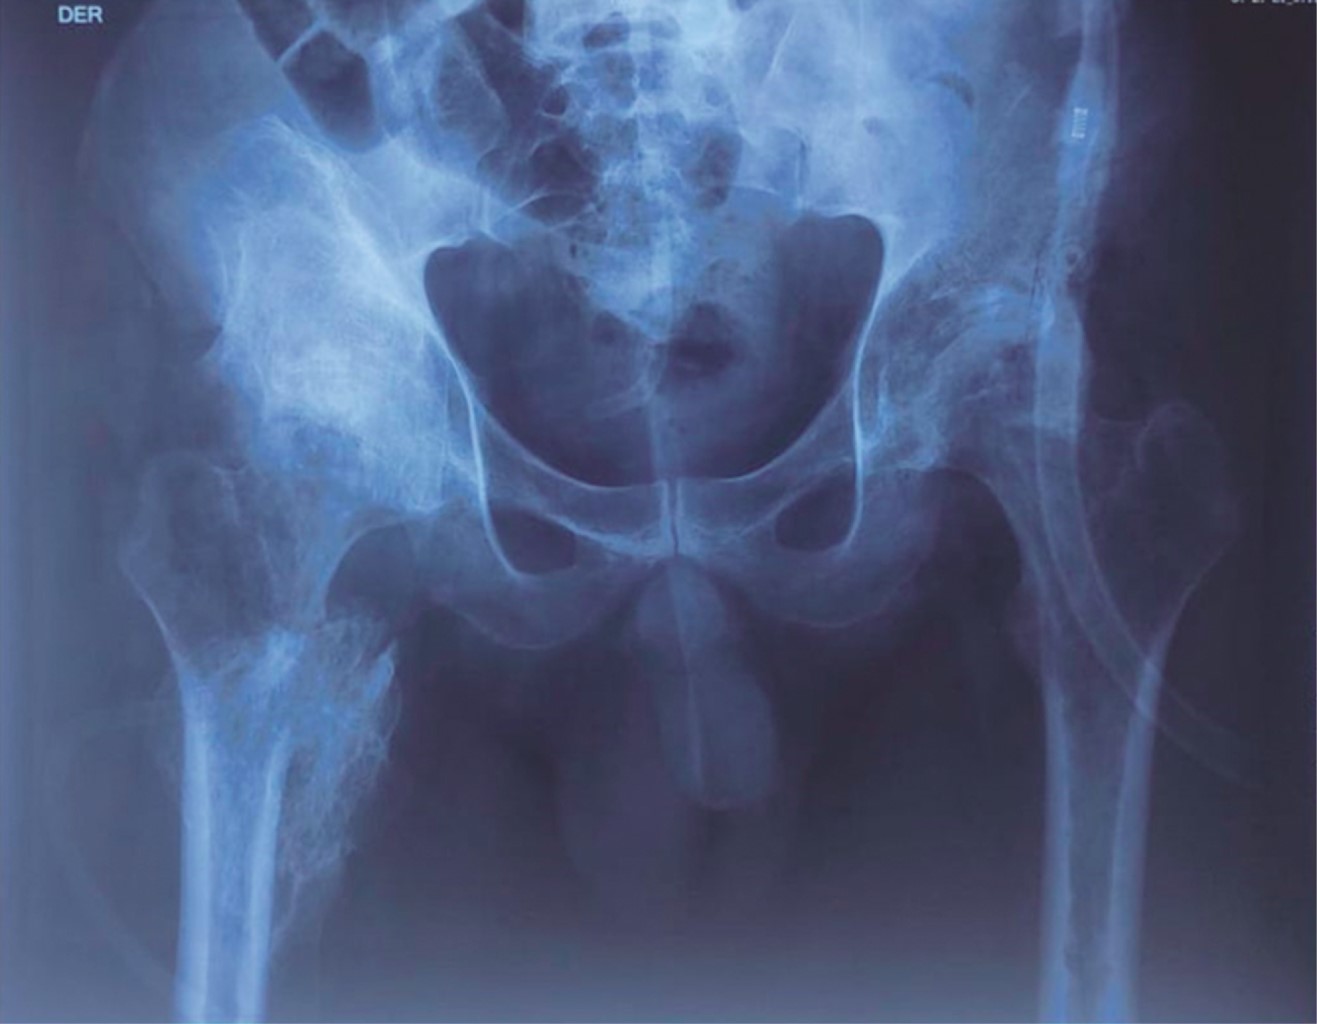

El paciente acudió a la consulta con estudios de rayos X y tomografía simple de pelvis (Figura 1). En la radiografía anteroposterior de pelvis se observa una lesión blástica a nivel de la cadera derecha de bordes regulares y bien definidos que involucra fémur proximal y fosa iliaca derecha en cadera contralateral datos de osteoartrosis coxofemoral. La tomografía muestra la misma lesión; sin embargo, en un corte sagital, se puede observar que el tejido óseo heterotópico se encuentra confinado al trayecto del musculo iliaco en forma de puente óseo entre la fosa iliaca derecha y el trocánter menor del fémur.

Figura 1